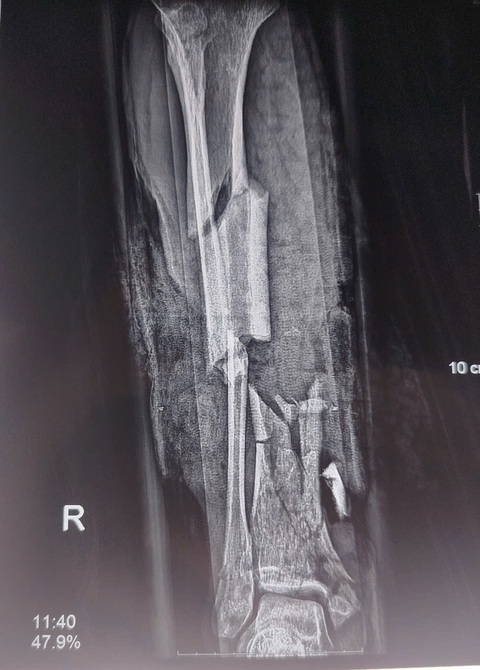

Bệnh nhân phải cắt cụt chân phải do bình gas mini phát nổ - Ảnh: BVCC

"Bệnh nhân bị nát cẳng chân phải, gãy hở cẳng chân trái, vết thương phức tạp bàn tay hai bên, chấn thương bụng kín.

Do mức độ tổn thương nặng, người bệnh phải phẫu thuật cắt cụt 1/3 cẳng chân phải. Đồng thời sửa mỏm cụt bàn ngón tay 4, 5; xử lý vết thương bàn tay hai bên", bác sĩ Sơn cho hay.